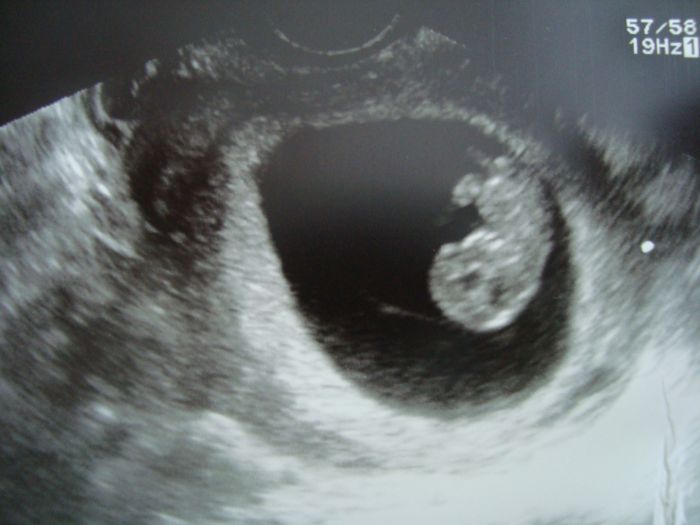

Dle PM 8+5, dle UZV 8+6. Velikost 22 mm, srdicko 170/min. Vice obrazek :-)

Vsechno je v poradku, za ctrnact dnu vsechny odbery na lacno a maly uzv, za dalsi dva tydny vysledky a velky uzv. Kortikoidy az podle vysledku, utrogestan dale. Protoze jsme o trosku starsi, nez jste byly vy, tak jsou tam ty 2 mm navic. Ale kazdy milimetr se pocita! Pustila mi i srdicko. Pritel jenom koukal, jak mu ukazovala, kde co je a nasel i srdicko. Ted byl chudak vynervovanejsi nez ja, kdyz porad rikam, jak mi nic neni, tak mel strach. A pritom se tam prvek tak hezky hemzi. Verim, ze ted uz bude vsechno dobre.

Fotecka je ve skutecnosti hezci, nejak to neslo lip vyfotit. Jsem rada, ze jsme nemuseli cekat, stacily ty nervy na genetice. Ja jenom koukala, jak prvek za dva a pul tydnu vyrostl. Pred tim cmouha v cerne kulicce a ted mimi mimi v docela velkem prostoru. Kdyz jsem rekla, ze mi nic neni, tak jako bych rekla, ze jsem snidala rohlik. A pak ze dobre, ze nezvracim. Tak asi to je fakt normalni. Ale prece jenom jsem radsi kdyz me pobolivaji prsa a obcas me treba zaboli v zadech :-)